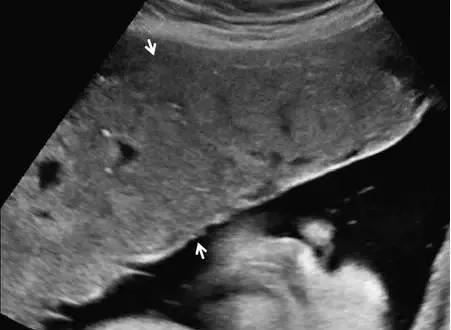

胎盘附着异常

胎盘附着异常:包括胎盘粘连、胎盘植入及胎盘穿透(图 11)。胎盘粘连指胎盘组织向子宫肌壁延伸,但并未对其构成实质性的侵袭,占所有胎盘附着异常的75%。

胎盘植入指胎盘组织已侵入子宫肌壁,但并未突破浆膜层。穿透指不仅侵入肌壁,且已突破至浆膜层之外,可导致子宫的毗邻器官如膀胱、肠管及腹壁受累。超声是本病的主要显像方法,在临床高度怀疑本病或超声检查为阴性或不确定时,可使用 MRI(图 12 和图 13)。

图 11 为胎盘附着示意图 ,自最左图向右分别为正常、粘连、植入、穿透

图 12 示胎盘粘连:A 为孕 32 周患完全性前置胎盘(此图未显示)孕妇的子宫前壁横切面(线阵探头所得),可见肌壁由上至下、向膀胱子宫陷凹方向逐渐缺乏、变薄(短箭头所示)。B 为另一孕妇的冠状位 MRI,孕期经常性左腹痛,超声考虑胎盘粘连,长箭头示胎盘下方的低信号肌壁由左向右逐渐变薄。此 2 例均在剖腹产时被证实为胎盘粘连

图 13 示合并有完全性前置胎盘的胎盘穿透,患者有 2 次剖宫产病史:A 为子宫纵切面,箭头示肌壁逐渐变薄、子宫与膀胱之间的界限模糊,胎盘下的闲置空间消失(B :膀胱)。B 为同一患者的子宫矢状面,箭头示大量不规则紊乱血流向肌壁延伸。图 C 为另一孕妇 28 周时的矢状位 MRI,可见前次剖腹产瘢痕上缘存在胎盘对子宫前壁的侵犯、肌壁连续性局部中断(箭头)